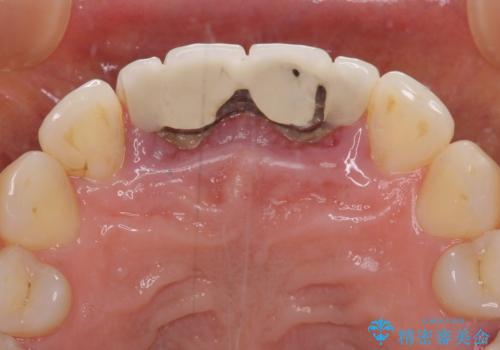

- 隙間の空いた前歯をセラミッククラウンで補隙したところ、歯肉から出血してしまい、何とかしたいとのことで来院された患者様です。

初めは前歯のみの処置で改善を希望されていたため、広範囲に処置範囲を広げることで歯の幅がバランスする治療を提案しましたが、削らなければならない歯が増えてしまうため、患者様と相談して全顎矯正により前歯のスペースを閉じていくこととしました。

不適合なクラウンが装着されていたため、歯周ポケットが深くなっていましたので、矯正治療前に歯周外科処置を行って歯周ポケットを除去し、矯正治療後にオールセラミッククラウンにて補綴治療を行うこととしました。